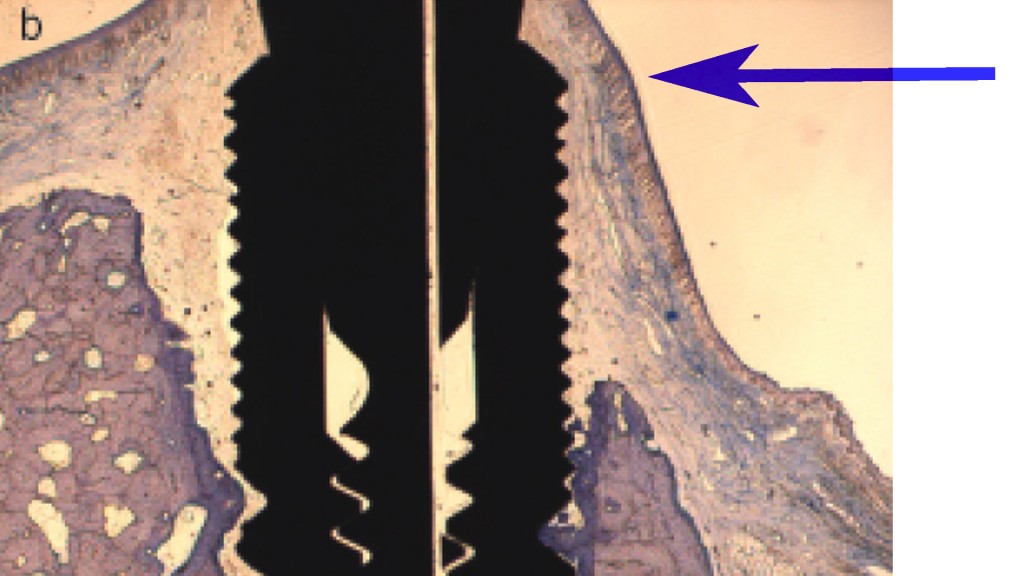

Ma guarda la cosa che più di tutte mi entusiasma di queste immagini:

Un sottilissimo ed instabile strato di gengiva rimane, chissà perché, “appeso” alla vite di guarigione e alla parte coronale dell’impianto che è ormai tutta fuori dall’osso. In pratica, se tu guardi questo impianto da vestibolare noterai una recessione vestibolare di molto inferiore rispetto a quella che avresti con la sola estrazione perché gli emidesmosomi rimangono appiccicati al titanio. Ma avrai comunque:

- Una certa recessione

- Scarsa stabilità del tempo visto lo spessore e la natura del tessuto

- Perdita di volume vestibolare con conseguente concavità dei tessuti rosa apicali alla corona e ombra scura antiestetica

- Grigio del titanio che traspare attraverso tessuti così sottili.